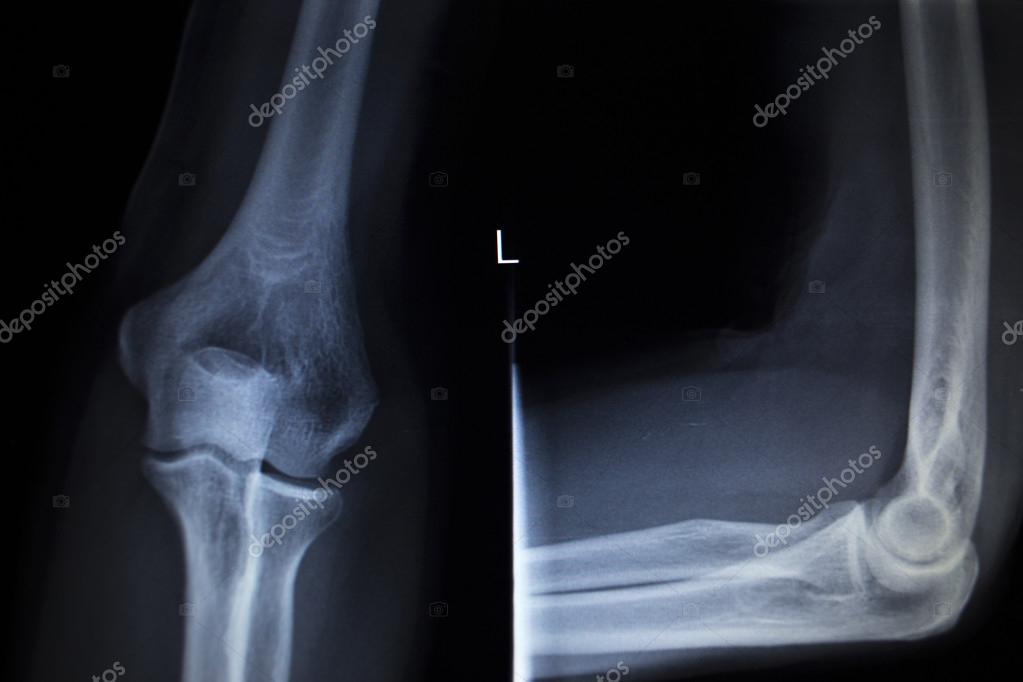

Lateral Xray elbow projection of the patient in Figure 1 Download

Lateral Xray elbow projection of the patient in Figure 1 Download Tennis Elbow X Ray Lateral epicondylitis is the most commonly encountered overuse syndrome in the elbow. Lateral epicondylitis, or tennis elbow, involves the muscles and tendons of the forearm that are responsible for the extension of your wrist and fingers. Lateral epicondylitis, also commonly referred to as tennis elbow, describes an overuse injury secondary to an eccentric overload of the. Tennis elbow (lateral epicondylitis). Tennis Elbow X Ray.